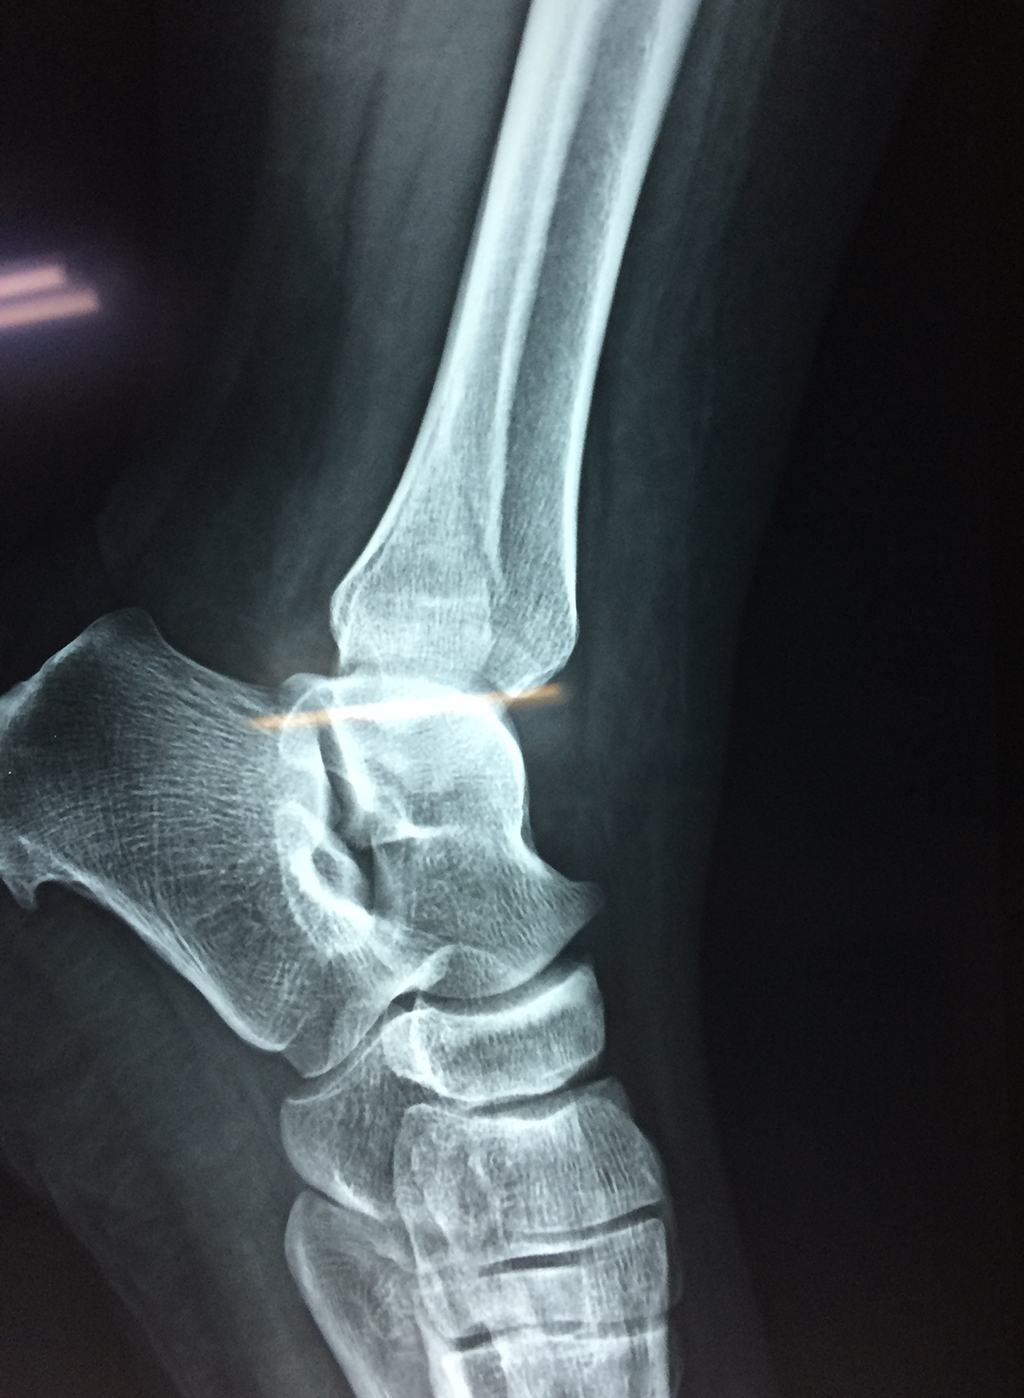

Una fractura de tobillo es la rotura de uno o más de los huesos del tobillo. Estas fracturas pueden ser:

- Parciales (el hueso está sólo parcialmente fisurado, no del todo).

- Completas (el hueso está perforado y está en 2 partes).

- Producirse en uno o ambos lados del tobillo.

Algunas fracturas de tobillo pueden requerir cirugía si:

- Los extremos de los huesos están desalineados entre sí (desplazados).

- La fractura se extiende hasta la articulación del tobillo (fractura intra-articular).

- Los tendones o ligamentos (tejidos que sujetan los músculos y los huesos entre sí) están rotos.

- El médico cree que sus huesos probablemente no sanen apropiadamente sin cirugía.

- El médico considera que la cirugía puede permitirle una recuperación más rápida y confiable.

- En los niños, la fractura involucra la parte del hueso del tobillo donde el hueso está creciendo.

Cuando se necesita cirugía, es probable que esta implique el uso de clavijas de metal, tornillos o placas para sostener los huesos en su lugar mientras la fractura se consolida. Los elementos de soporte pueden ser temporales o permanentes.